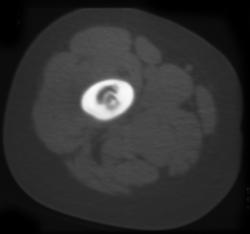

Posterior Right Clavicular Dislocation